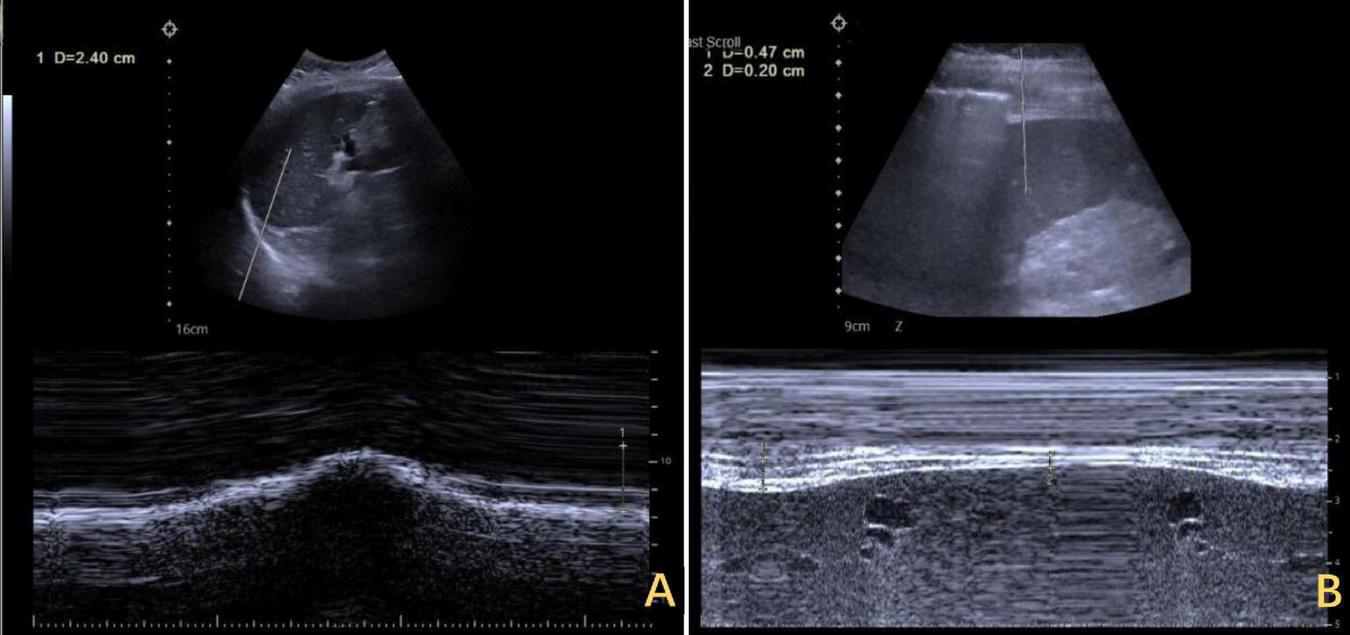

FIGURE 5

Ultrasound assessment of bilateral diaphragm amplitude. (A) The left diaphragm showed an amplitude of 2.4 cm at end of inspiration. (B) The right diaphragm exhibited minimal amplitude throughout the respiratory cycle, ranging from 0.20 to 0.47 cm.

However, the patient’s treatment process was not very smooth, and the patient experienced twists and turns. The treatment of BCS began with an interventional approach using a balloon to dilate and shape the stenotic IVC. The patency of the IVC was restored after balloon inflation (Figure 3A), but the original stenosis returned immediately after balloon withdrawal, and there was no change in the internal diameter of the stenosis (Figure 3B). There was no benefit from three rounds of balloon inflation. Postoperative chest radiographs showed a marked elevation of the right diaphragm in contrast to the left diaphragm, which was elevated by approximately three vertebral levels, consistent with a diagnosis of DE (Figure 4A). Subsequently, ultrasound examination of diaphragmatic mobility revealed that during calm breathing, the right diaphragm amplitude was 0.20–0.47 cm and did not change significantly; the left diaphragm amplitude was 2.4 cm; which was consistent with the diagnosis of right DE (Figure 5). Tumors of thoracic and mediastinal origin and those caused by inflammation were ruled out by positron emission tomography/computed tomography (PET/CT). Based on these findings, the CT images were further reviewed. It was suggested that the elevation of the diaphragm led to liver transposition and torsion of the HV at the confluence of the IVC. This approach helped to clarify the distortion of the IVC despite several interventional balloon dilatations due to the external force exerted by liver traction. To prevent further elevation of the diaphragm from worsening the obstruction, DP was recommended by thoracic surgeons. However, the efficacy of this procedure for treating BCS is inconclusive and has not been reported in the literature. Nonetheless, DP minimally invasive, and even if it is ineffective, it does not increase the difficulty of open surgery.